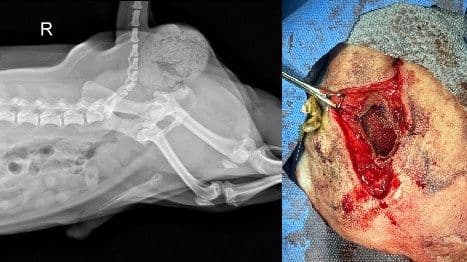

PSS (간문맥 전신 단락)

내외과 협진 고난이도 수술